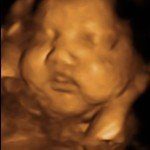

4D/5D/HD Ultrasound Gallery

Gallery